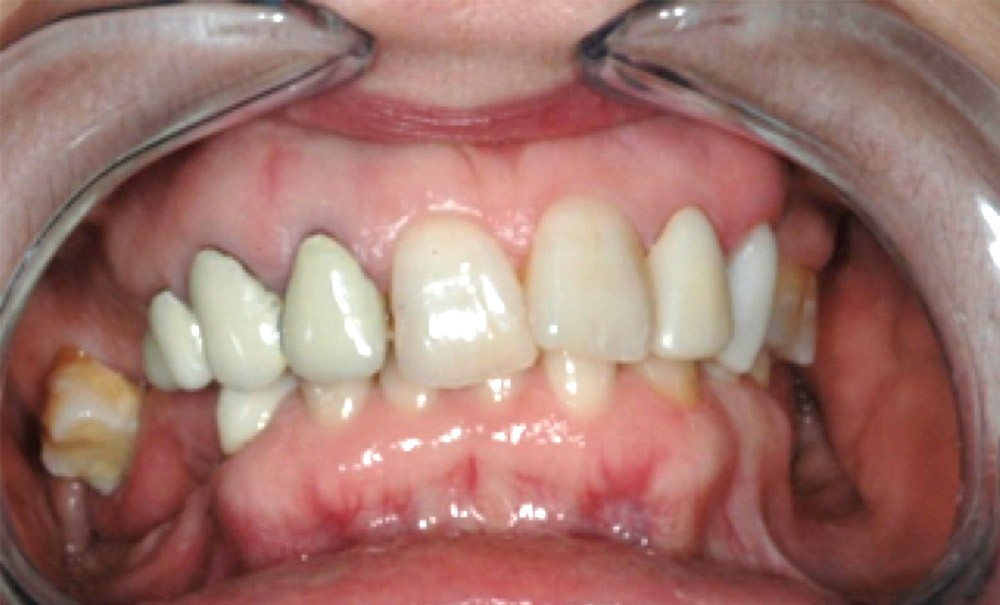

Cet article présente un cas clinique dont l’objectif d’illustrer les étapes diagnostiques et thérapeutiques à mettre en œuvre lors d’une reconstruction occluso-prothétique dans une position thérapeutique corrigeant la relation intermaxillaire initiale.

Les chirurgiens-dentistes sont parfois confrontés à des réhabilitations orales complexes. Les difficultés peuvent être dues à des délabrements ou des migrations dentaires, des affrontements occlusaux chaotiques, mais aussi à une relation dento-squelettique défavorable. Cela s’accompagne souvent d’une usure excessive des dents plus ou moins associée à une perte de dimension verticale. Les praticiens se rendent compte que ces usures se sont développées sur de nombreuses années en modifiant également les relations intermaxillaires. Cette modification constitue ainsi une réponse adaptative à l’évolution continue des usures/délabrements des dents. Ces situations nécessitent souvent une reconstruction de l’architecture occlusale, avec parfois une modification de la relation intermaxillaire et non pas une restauration prothétique dans le contexte existant.